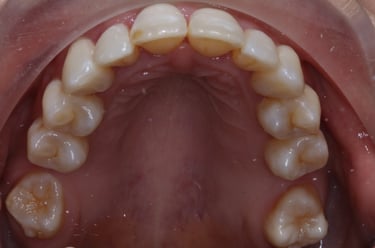

Before & After photos

before

after

Case Example =full set of photos